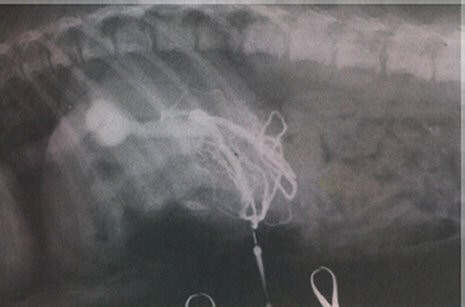

Contrast radiography. Note the passage of contrast agent from the exteriorized

jejunal vein directly to the caudal vena cava without significant flow to the liver

(photograph courtesy of P. Watson, University of Cambridge).